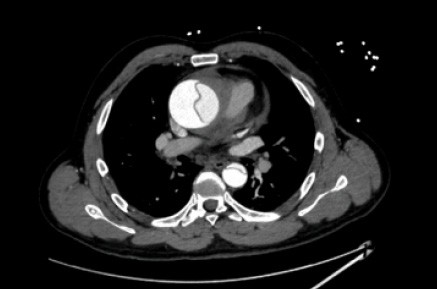

49세 여성이 갑작스러운 호흡곤란과 함께 심한 가슴 통증을 호소하며 내원하였다. 통증은 등 쪽으로 방사되고 있으며, 약물 치료에도 통증이 지속되고 있다. 흉부 CT 스캔 결과 대동맥 벽에 이상이 관찰되었다. 이 환자에게 필요한 응급 처치는 무엇인가?

Imp: Aortic dissection, Stanford type A

상행대동맥에서 false lumen이 보이는 stanford Type A 대동맥박리다. Stanford Type A의 치료는 대동맥 치환술이 필요하다.

• 지문의 CT